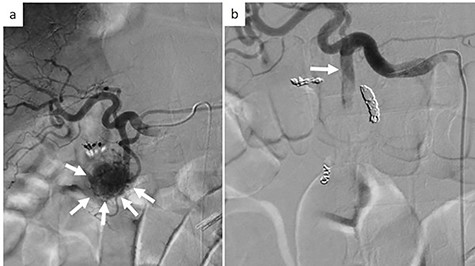

On examination, the patient had conjunctival pallor, blood pressure: 147/79 mmHg after transfusion and pulse: 95 beats per minute. Laboratory blood tests revealed a hemoglobin level at 7.8 g/dl. We decided to perform an emergency angiography which revealed a highly vascularized tumor at the pancreas head (Fig. 1a). The tumor was supplied with blood from a branch of the gastroduodenal artery. No extravasation of contrast medium was observed. Embolization of the anterior superior pancreatoduodenal artery and the right gastric epiploic artery was performed, and then also of the gastroduodenal artery, the right gastric epiploic artery, and the gastroduodenal artery. Angiography thereafter confirmed that all feeder arteries of the tumor had been embolized (Fig. 1b). Gastrointestinal hemorrhaging ceased after embolization. The patient did not complain of any abdominal pain after embolization and his medical condition was stable.

Emergency angiography; (a) emergency angiography showing the hypervascular tumor in the pancreas head (white arrow); (b) embolization of the gastroduodenal artery (white arrow).